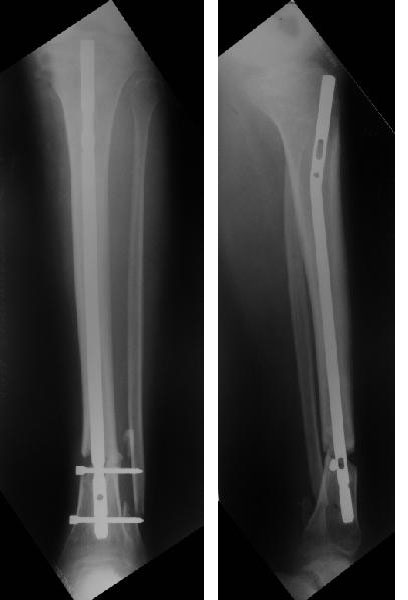

Здравствуйте коллега! Интересный случай! Буквально 3-4 месяца назад столкнулся с подобной ситуацией. Плюс у больного имелась нейропатия малоберцового нерва, стойкая эквинусная деформация стопы. Молодой человек лечился в другом лечебном учреждении. Первым этапом выполнено удаление стержня ChM, наложен аппарат внешней фиксации, в течении недели проводилось устранение имеющихся деформаций. Вторым этапом выполнен ЗИМО стержнем MetaDiaFix-T большего диаметра (картинки в приложении).